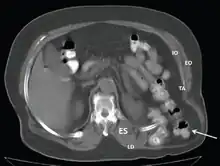

- CT scan-Grynfeltt-Lesshaft hernia.